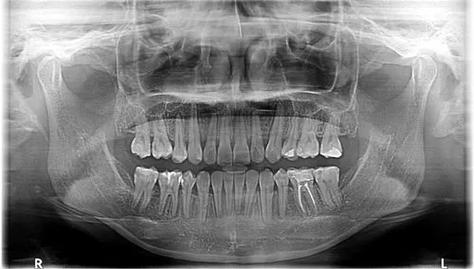

| 初诊检查项目 | 口腔检查、全景片(曲面断层片)、头影测量、模型分析,部分需做CBCT |